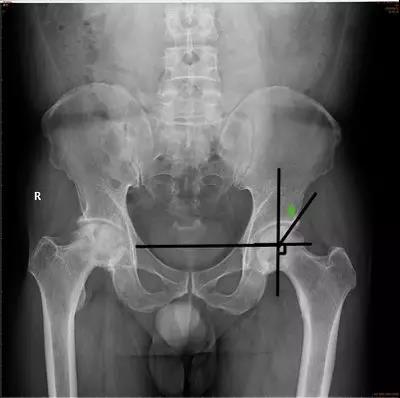

- CE角(Wiberg 的中心边缘角):即两侧股骨头中心连线的垂线和髋臼外缘股骨头中心连线所成的夹角。

- 正常值:20°~35°

- 临床意义:主要用于评估髋臼的包容性,髋臼发育不良时夹角变小。